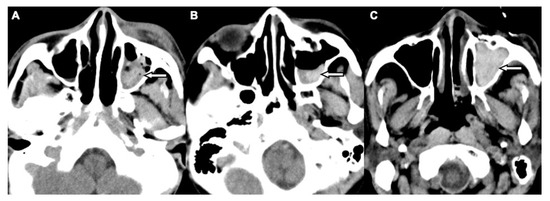

Two board-licensed radiologists (L.D.J. and Y.Y.C.) who were blinded to the patients’ clinical information reviewed only the head CT images by means of consensus. The radiologists were permitted to manipulate the window and level of the images. The CT variables related to the cranium included intracranial hemorrhage (ICH; epidural hemorrhage, subdural hemorrhage, subarachnoid hemorrhage, and intracerebral hemorrhage), and skull fractures. The CT variables related to OFFs included orbital floor discontinuity (Figure 1), gas bubbles entrapped between the floor fragments (Figure 1), inferior extraconal emphysema (Figure 2), orbital fat herniation into the maxillary sinus (Figure 2), and ipsilateral maxillary hemosinus (MHS, Figure 3). MHS was defined as high-attenuation opacity at the dependent portion of the maxillary sinus measuring ≥ 45 Hounsfield units (HU) as the lower limit of attenuation for clotted blood [15]. Since MHS is a relevant indicator used to detect OFFs on CT scans [5,16], we further classified MHS into the following three CT subtypes: (1) Type 1, high-attenuation opacity mixed with mottled gas (Figure 3A); (2) Type 2, air–fluid level (Figure 3B); and (3) Type 3, full opacification of the sinus (Figure 3C).

The sensitivity, specificity, positive predictive value, and negative predictive value of MHS and its three subtypes were evaluated in detail (Figure 4). While MHS exhibited a very high negative predictive value (99.7%) for excluding OFFs, type 1 MHS had the highest positive predictive value (69.5%) for detecting OFFs compared to total MHS and the other two subtypes.

A subset imaging analysis for head trauma patients with MHS was conducted to investigate the correlation between subtypes of MHS and OFFs. Patients with non-orbital floor fractures which may result in MHS (sole maxillary bone or medial orbital wall, or both) were excluded from the non-OFF group. The comparisons of head CT variables between the OFF (n = 188) and non-OFF (n = 102) groups are shown in Table 3. The OFF group more commonly exhibited type 1 MHS, while types 2 and 3 MHS were more frequently observed in the non-OFF group. In the multivariate logistic regression analyses, after adjusting for other CT variables, only type 1 MHS remained an independent risk factor of OFFs in these patients (OR, 47.50; 95% CI, 8.26–273.05; p < 0.001).

Figure 3. CT images showing three patterns of MHS related to OFFs associated with head trauma. (A) Type 1: high-attenuation opacity mixed with mottled gas in the left maxillary sinus (arrow) in a 52-year-old male with motorcycle crash-related head trauma. (B) Type 2: air–fluid level in the left maxillary sinus (arrow) in a 26-year-old female with motor vehicle collision-related head trauma. (C) Type 3: full opacification of the left maxillary sinus (arrow) in a 79-year-old male with fall accident-related head trauma.